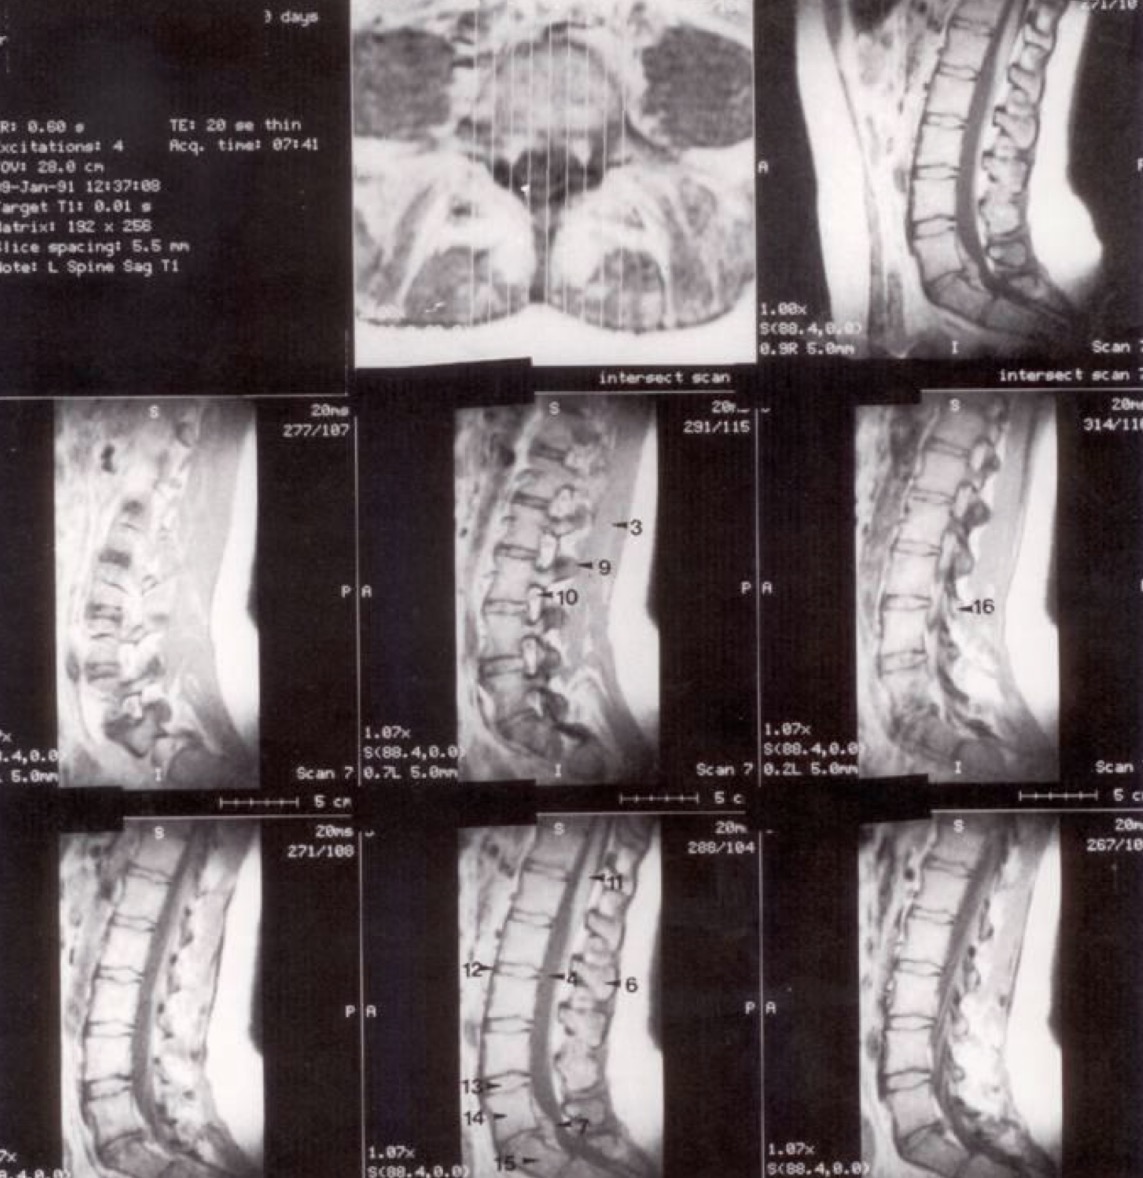

Metodika (a)

Horizontalūs (ašiniai) pjūviai per lumbosakralinę dalį. Pirmasis pjūvis yra žemiausias, kiti trys kyla į viršų per L IV - V diską.

Metodika (b)

Sagitaliniai (šoniniai) pjūviai. Vidurinis pjūvis matomas viršutinėje eilėje dešinėje, kiti seka eilės tvarka iš kairės į dešinę.

Klinikinis pastebėjimas

Mažas atstumas tarp stuburo ir priekinės pilvo sienos rodo, kad pacientas yra jaunas ir lieknas (mažai visceralinių riebalų).

1

M. rectus abdominis (tiesusis pilvo raumuo)

2

M. psoas major (didysis juosmens raumuo)

3

M. erector spinae (nugaros tiesiamasis raumuo)

4

Subarachnoidinė ertmė (spatium subarachnoidale)

5

Ganglion spinale (nugarinis mazgas)

6

Processus spinosus

7

L V - S I disko išvarža (protrūzija/ekstruzija atgal)

8

Tarpslankstelinė anga (tarp L V ir S I dešinėje)

9

Processus articularis superior L III

10

Nervinė šaknelė (radix spinalis)

11

Nugaros smegenys (medulla spinalis)

12

Ligamentum longitudinale anterius (priekinis išilginis raištis)

13

Tarpslankstelinis diskas (tarp L IV ir L V)

14

Corpus vertebrae L V

15

Corpus vertebrae S I

16

Processus articularis inferior L III